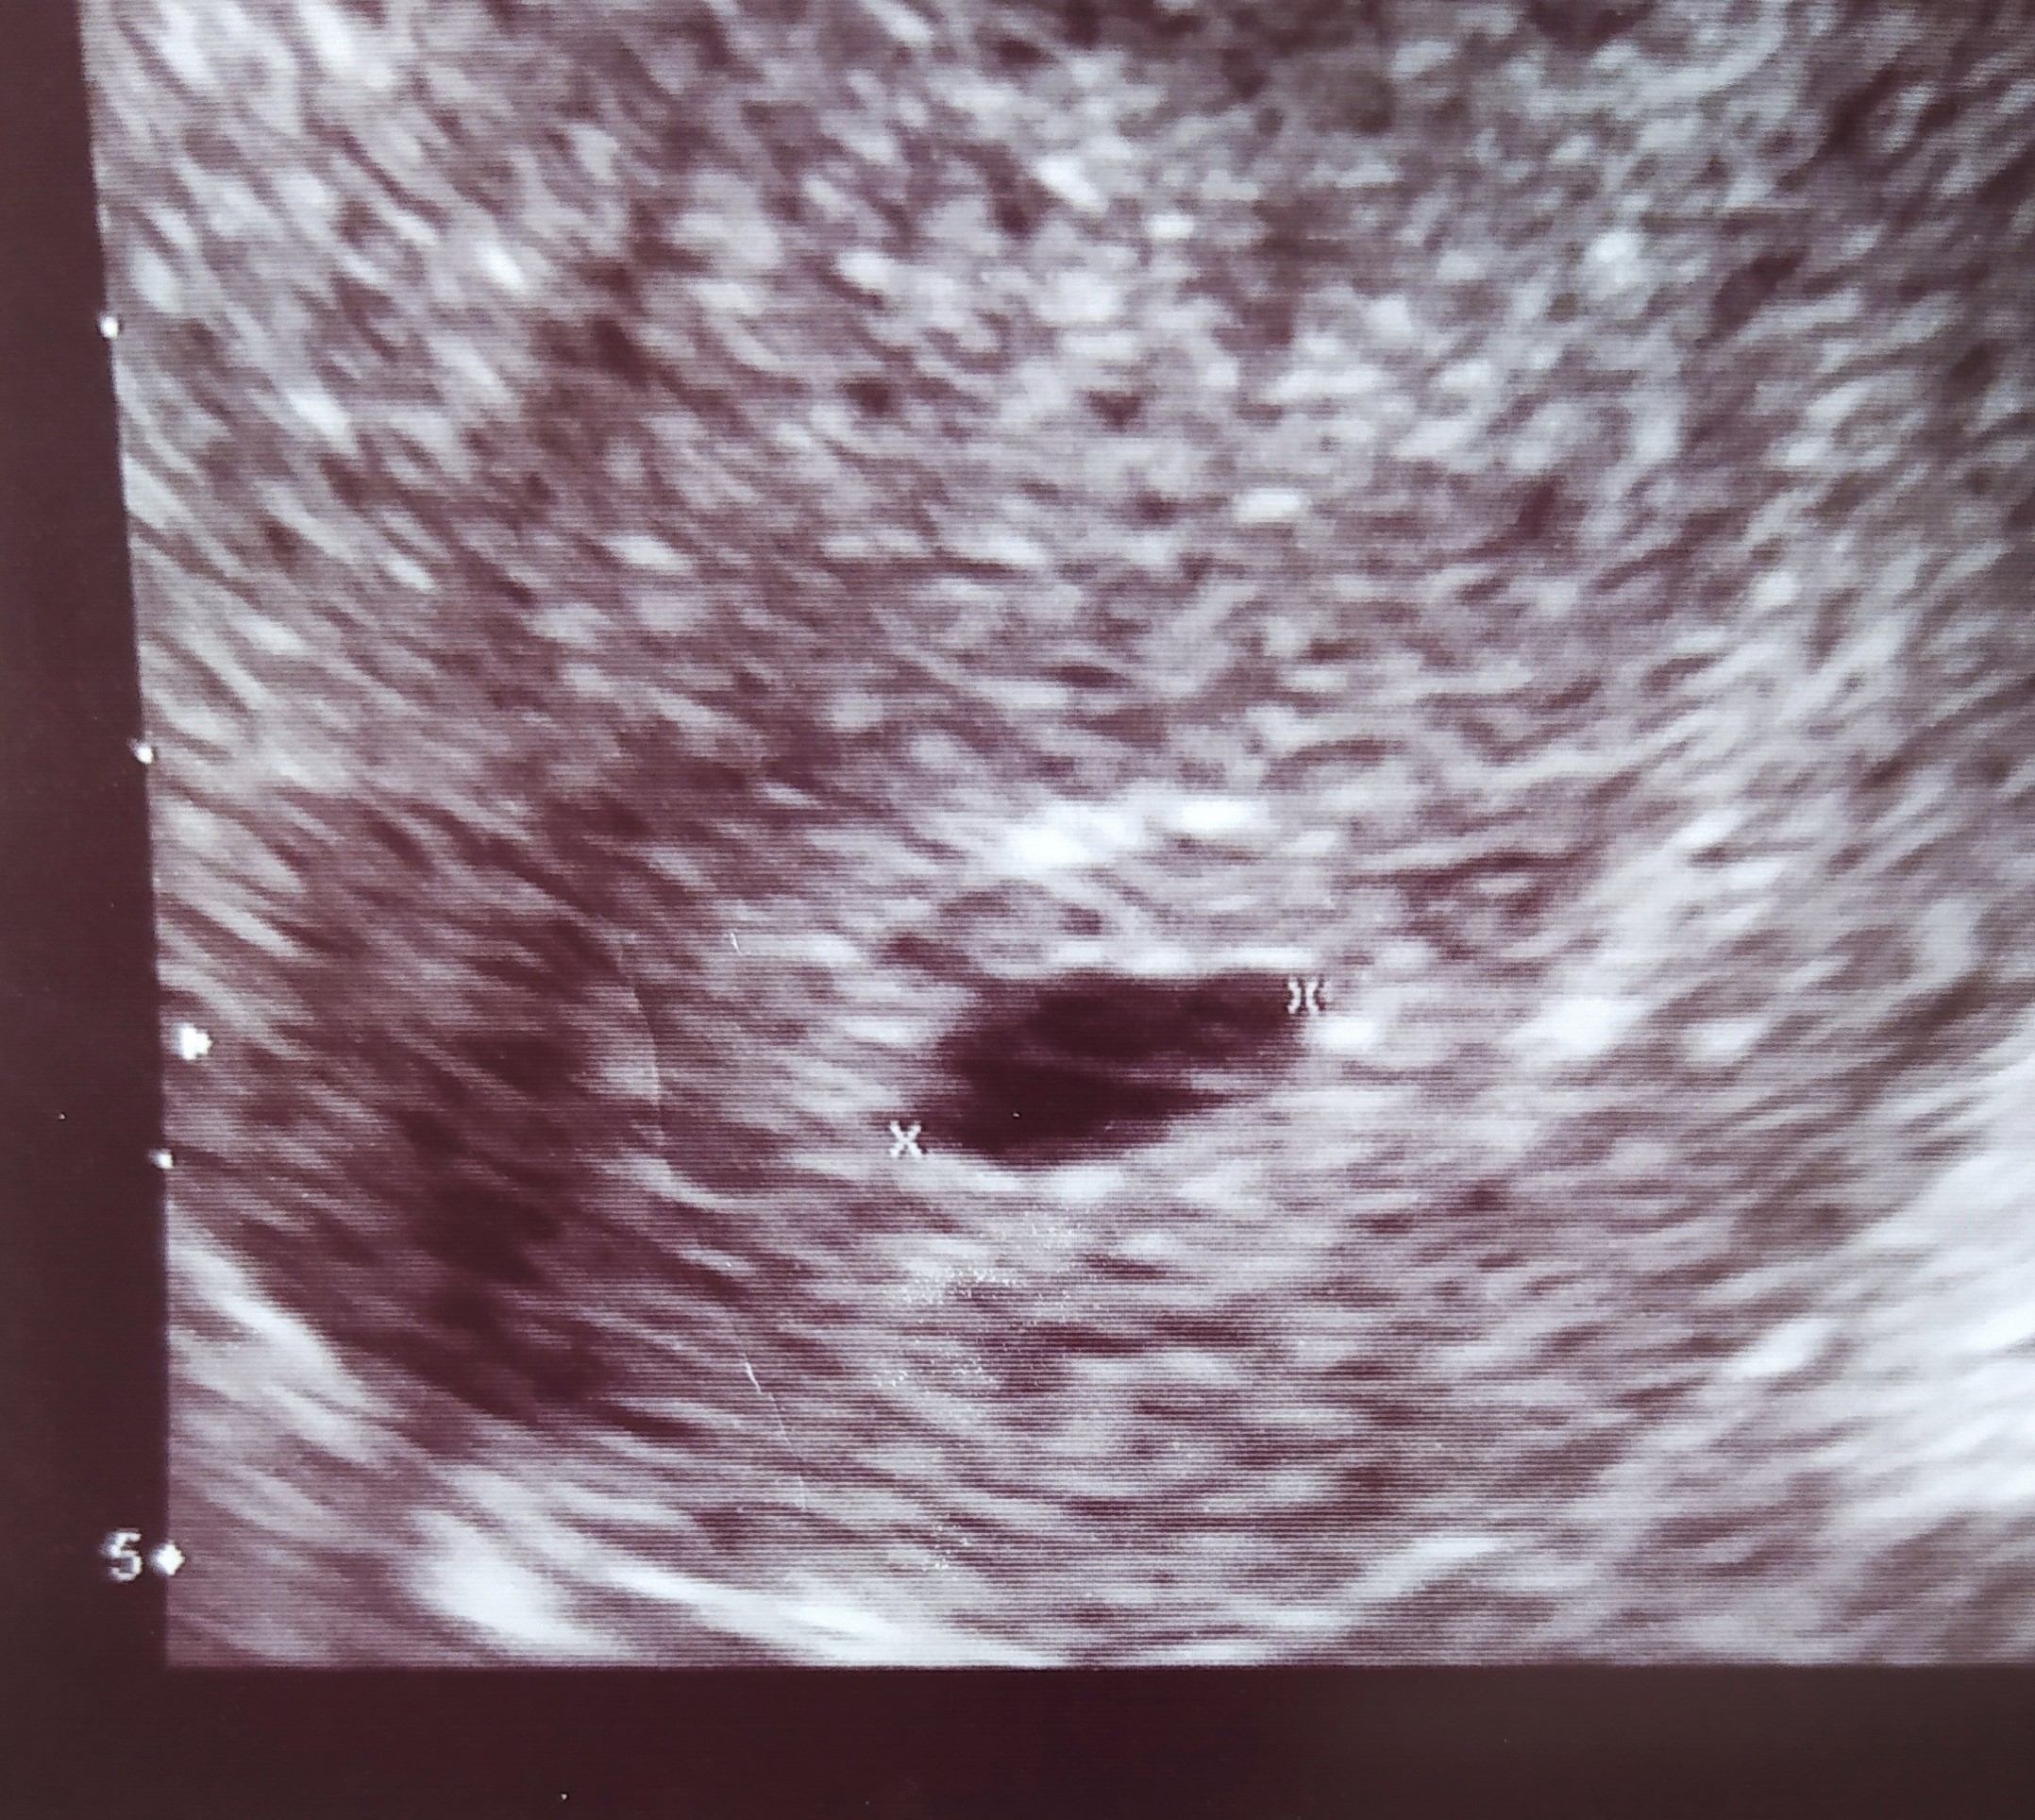

Więc beta sie rozbujala... Byłam na USG 13.07 wiec przy tak wysokiej becie powinno być widać coś więcej niż pusty pęcherzyk, który wielkością jest mniejszy niż wielkość z om, seks najpóźniej w cyklu był 17.06. Pęcherzyk wygląda tak. Ma na środku jakaś dziwna kreseczkę. Czy to może dwa pęcherzyki obok siebie? Lekarz nie wiedział, co to za kreseczka. Następna wizyta 27.07

IMG_20220720_115148.jpg